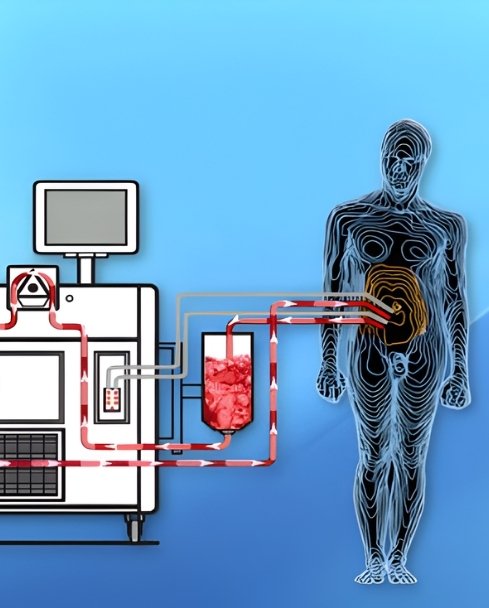

Hyperthermic Intraperitoneal Chemotherapy (HIPEC) is an advanced and highly specialized cancer treatment designed for patients with cancers that have spread to the lining of the abdominal cavity (peritoneum). This approach combines extensive tumor-removal surgery with direct, heated chemotherapy delivery, targeting cancer cells at their source. HIPEC allows oncologists to treat peritoneal disease more aggressively and precisely, offering selected patients improved disease control, reduced recurrence risk, and better long-term outcomes compared to systemic chemotherapy alone.

HIPEC is a procedure performed immediately after cytoreductive surgery, during which heated chemotherapy is circulated throughout the abdominal cavity before surgical closure.

Unlike intravenous chemotherapy, HIPEC delivers high concentrations of anticancer drugs directly to the affected surfaces, allowing better penetration into residual microscopic cancer cells while minimizing exposure to the rest of the body.

The heat enhances the effectiveness of chemotherapy by increasing cancer cell sensitivity and improving drug absorption at the cellular level.

Heated Chemotherapy Circulation

Chemotherapy solution heated to 41–43°C

Circulated within the abdomen for 60–90 minutes

Continuous movement ensures uniform drug distribution

Heat enhances chemotherapy effectiveness by damaging cancer cells and increasing drug penetration.

Targeted Local Therapy Advantage

High local drug concentration at tumor sites

Limited systemic absorption and toxicity

Improved effectiveness against microscopic residual disease